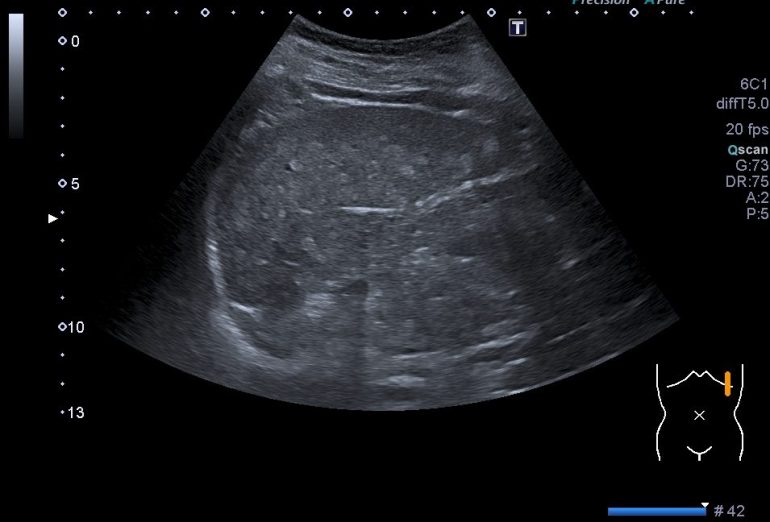

Tras ver las imágenes vas a comprobar como la estructura está dañada, pero primero quiero que veas como se ve una ecografía normal del bazo, ecoestructura que, si estás empezando se resiste, su ubicación en el abdomen, protegido por las costillas, cercano al ángulo esplénico del colon, hace que sea complicado, ten paciencia, solo con esto conseguirás estudiarlo bien, es cuestión de técnica.

Estas dos imágenes superiores son la normalidad. Corte axial y longitudinal del Bazo. Homogéneo, sin lesiones, grande sin llegar a la esplenomegalia. Bazo de libro.